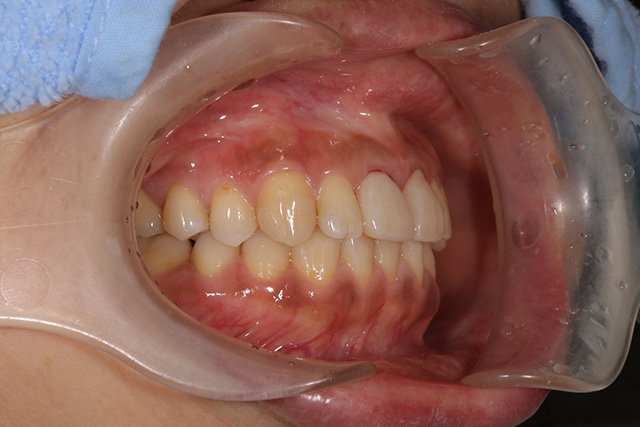

審美症例